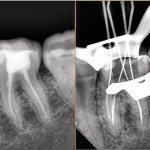

Пример восстановления зубов методом имплантации: